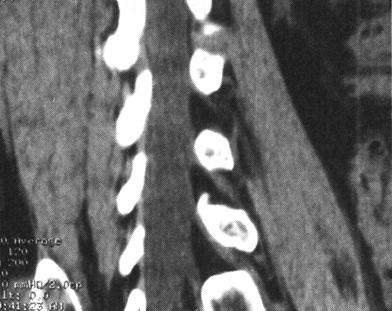

图7-14 腰椎后柱骨折伴硬膜外出血,马尾受压。T1W(a)和T2W(b)矢状成像,椎管后方硬膜外可见T1W和T2W均为高信号的血肿